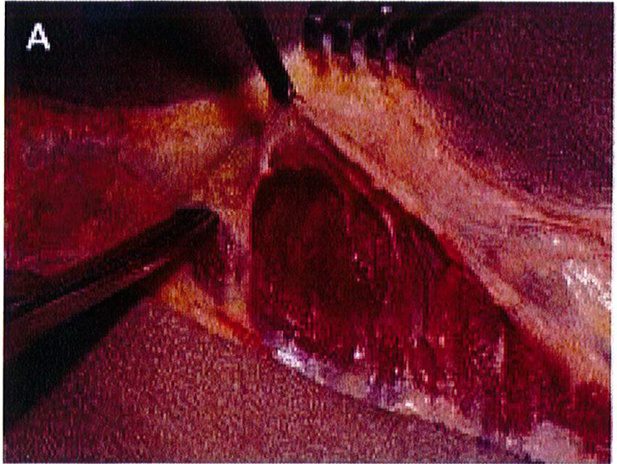

Hình. 3. (A) Lớp cân mạc che phủ cơ mông lớn. (B) Bóc tách lớp cân và cơ để tạo mặt phẳng cấy ghép. (Trích từ de la Pena JA, Rubio OV, Cano JP, et al. Subfascial Nâng mông. Clin Plast Surg 2006;33:409; đã xin phép trước khi đăng tải.)

của chúng. Cân cơ mông lớn – nhõ đều đi cùng với chiều hướng của lớp cơ chúng che phủ. Nên nhớ hệ thống cân cơ này buộc phải bảo tồn tối đa trong bất kỳ phẫu thuật nâng mông thẩm mỹ nào. Và khối implant khi đặt ở vị trí dưới cân sẽ đảm bảo không ảnh hưởng tới bất kỳ cấu trúc mạch máu thần kinh sâu nào (Hình 3).